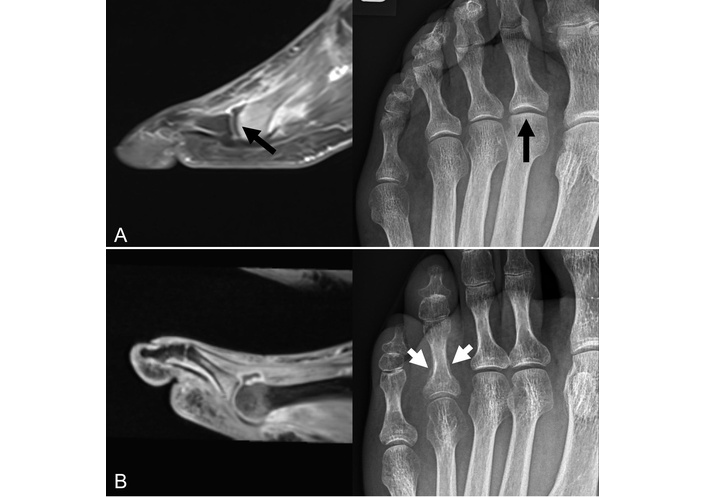

Sagittal contrast-enhanced T1w fat-saturated MRI (left figures) of the forefoot and corresponding X-rays (right figures) of two patients. (A) Images of a 66-year-old female patient presenting with foot pain under suspicion of arthritis. The MRI shows a subchondral fracture of the 2nd metatarsal head. Both radiograph and MRI demonstrate some linear subchondral sclerosis and loss of sphericity of the articular surface due to an infraction (black arrows). (B) Images of a 51-year-old male patient with long-standing axSpA with peripheral involvement, no fracture. The MRI demonstrates dactylitis of the 4th toe with dominant arthritis of the metatarsophalangeal joint, while the X-ray shows a mineralized periostal reaction of the proximal basophalangeal metadiaphysis (white arrows). axSpA: axial spondyloarthritis; MRI: magnetic resonance imaging; T1w: T1-weighted. Reprinted from [31]. © 2023 by the Journal of Rheumatology.